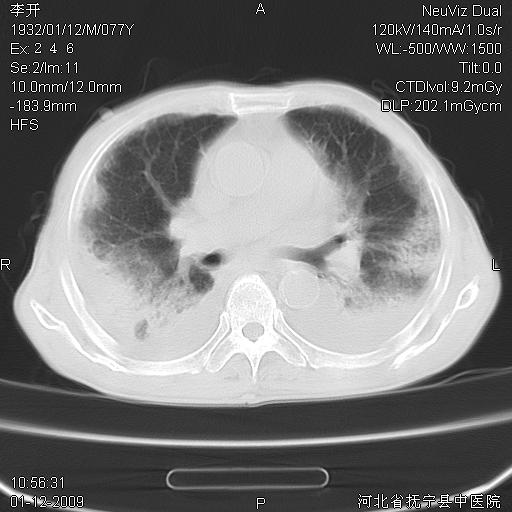

以下是引用黑白光影在2009-1-19 16:49:00的发言:[br]心衰肺水肿;心包、胸腔积液;冠脉钙化;肺部感染。